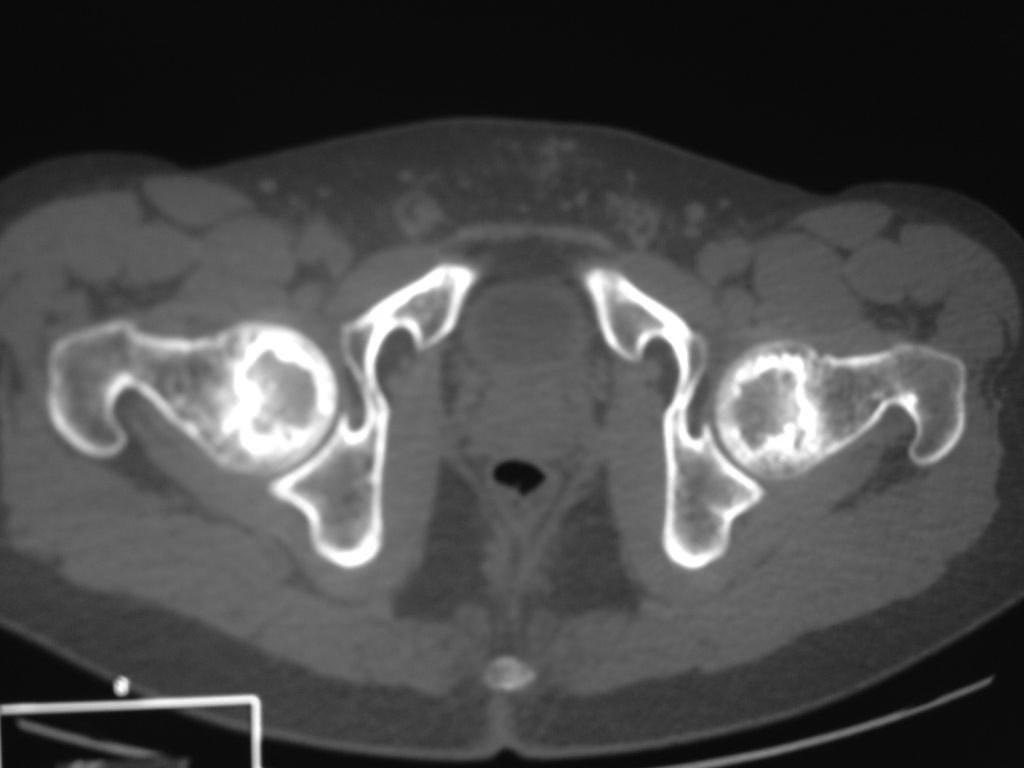

Уважаемый доктор, скорее всего- некроз(инфаркт ) костного мозга (двухсторонний)

AVN. Синонимы: ишемический костный некроз, костный инфаркт, костный некроз, асептический некроз.

Возможно сомнения в диагностике связаны с нетипичной рентгенологической картиной. На снимке большая киста, которая расположена в центре головки, а при АВН начинается в верхней нагрузочной зоне. Отсутствует коллапс, сохранилась сферичность головки; не очень выраженный, но характерный признак "Crescent Sign".

Диффернциальную диагностику надо делать с доброкачественной кистой или метастазами. Но двухсторенная киста встречается очень редко, и киста в шейке распологается более дистально, чем при АВН. Гетерогенная картина головки немного напоминает метастаз, но без первичной опухоли и затяжной характер течения заболевания снимает подозрение на злокачественный процесс.